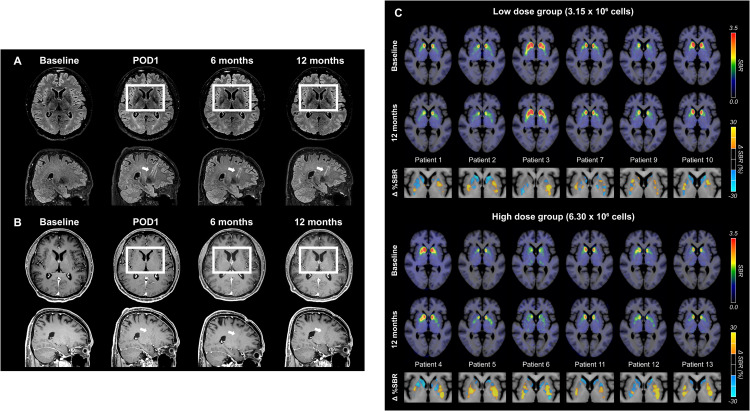

術(shù)后MRI顯示,移植區(qū)域未出現(xiàn)腫瘤或明顯炎癥反應(yīng),細(xì)胞被準(zhǔn)確植入殼核目標(biāo)區(qū)域,初步證明手術(shù)和細(xì)胞定位的安全性與可控性。

更關(guān)鍵的證據(jù)來自多巴胺轉(zhuǎn)運(yùn)體PET成像。與基線相比,后背側(cè)殼核區(qū)域的DAT信號(hào)在高劑量組明顯升高,且這種變化與患者停藥狀態(tài)下的運(yùn)動(dòng)改善程度呈顯著相關(guān)。這意味著,影像學(xué)上觀察到的多巴胺能功能增強(qiáng),與臨床癥狀的改善方向一致。(圖6)

這些結(jié)果共同表明:移植的多巴胺祖細(xì)胞不僅在腦內(nèi)存活,而且在關(guān)鍵運(yùn)動(dòng)環(huán)路中實(shí)現(xiàn)了功能性整合,并與實(shí)際運(yùn)動(dòng)改善相對(duì)應(yīng)

圖6:代表性腦部MRI圖像以及A9-DPC移植后18F -FP-CIT攝取量的個(gè)體水平變化